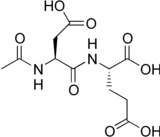

| Systematic IUPAC name

(2S)-2-[(2S)-2-Acetamido-3-carboxypropanamido]pentanedioic acid | |

| C11H16N2O8 | |

| Molar mass | 304.255 g·mol−1 |

N-Acetylaspartylglutamic acid (N-acetylaspartylglutamate or NAAG) is a peptide neurotransmitter and the third-most-prevalent neurotransmitter in the mammalian nervous system. NAAG consists of N-acetylaspartic acid (NAA) and glutamic acid coupled via a peptide bond.